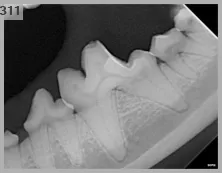

九歲的米米是個健康的老狗狗,牙齒在主人細心維護下基本上沒有太大的問題。就在這次的年度牙周檢查下,發現了左下第一大臼齒有一個小缺損......

所有存在任何損傷類型的牙齒均應接受放射學檢查,以判別是否存在炎症反應。

幸運的是,

米米在檢查下並沒有出現感染或牙髓腔暴露的情形,

因此最後將他以補牙的方式補起來,

避免未來形成敏感性牙齒的可能。